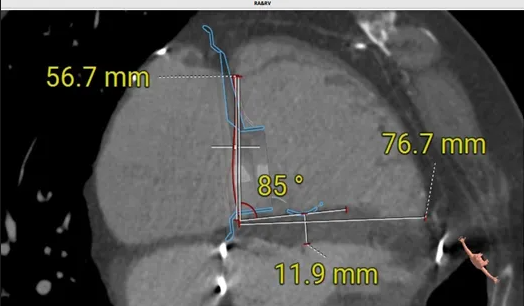

術前心臟CT評估

三尖瓣環切線位夾角 85°